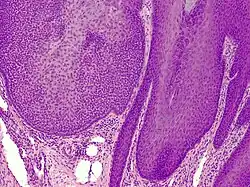

Trichilemmoma (also known as "tricholemmoma"[1]) is a benign cutaneous neoplasm that shows differentiation toward cells of the outer root sheath.[2]: 673 [3] The lesion is often seen in the face and neck region. Multifocal occurrence is associated with Cowden syndrome, in which hamartomatous intestinal polyposis is seen in conjunction with multiple tricholemmoma lesions.

A trichilemmoma on a forehead